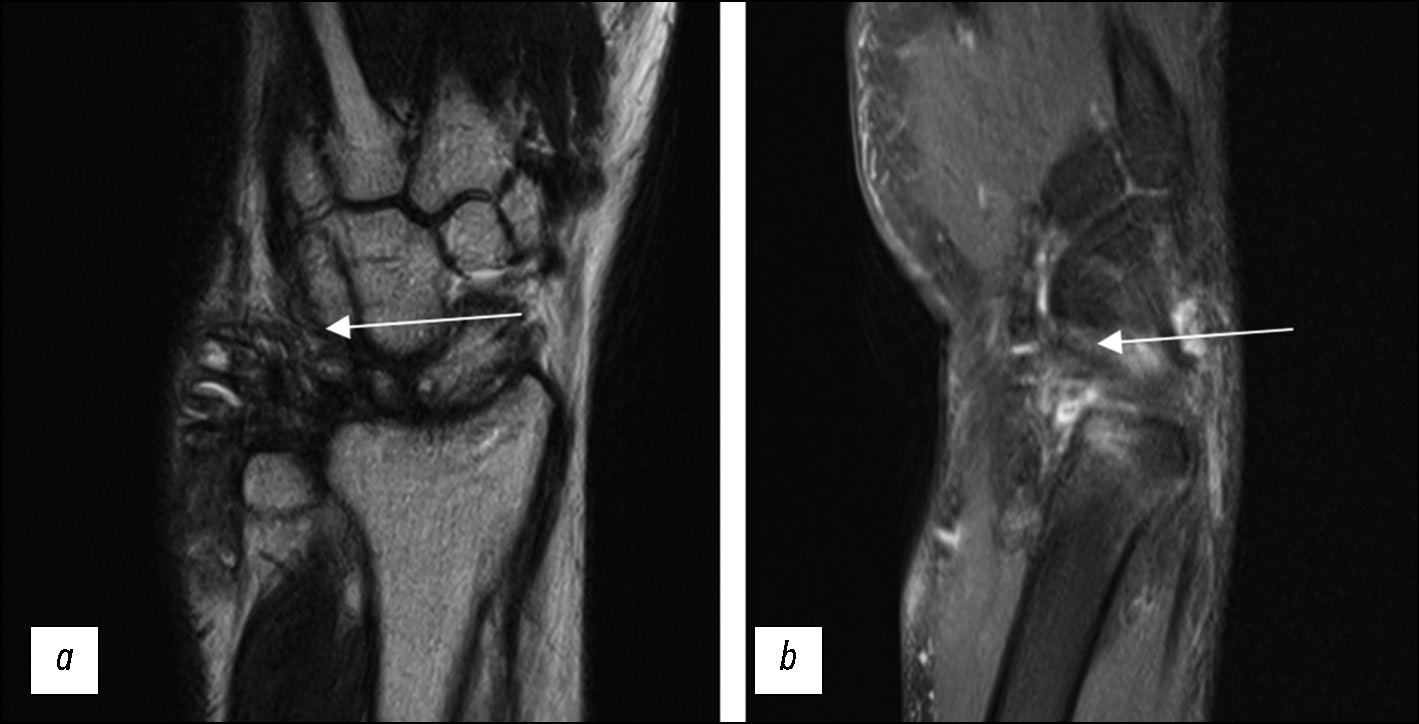

Fig. 8. Reduced imaging quality because of movement artifacts without using a splint (arrows); (a) T1-weighted images in the coronal plane; (b) STIR protocol in the coronal plane.

Fig. 9. Reduced imaging quality in a patient with triangular fibrocartilage complex disorder because of motion artifacts (arrows) and atypical positioning (without a splint); (a) T2-weighted images in the coronal plane; (b) PD-weighted images with fat suppression in the sagittal plane.